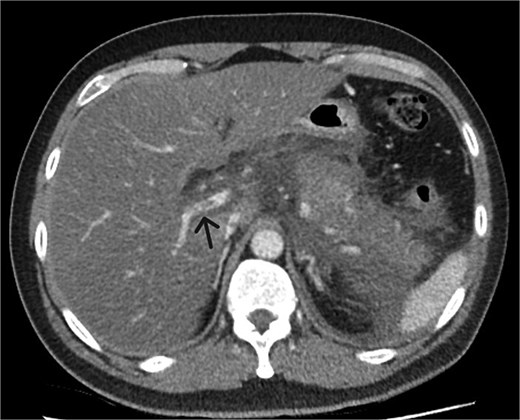

A 39-year-old male presented with one week of worsening epigastric pain radiating to the back, with vomiting, jaundice, and dark urine. His past medical history included depression and alcohol-related liver disease without cirrhosis. On admission he was afebrile, had a soft abdomen with epigastric tenderness worse on palpation, tachycardic, and normotensive. Initial investigations showed a lipase of 2600 U/L, C-reactive protein 238 mg/L, lactate 3.4 mmol/L, and bilirubin 100 μmol/L (Table 1). Abdomen and pelvic computer tomography (CT) demonstrated body and tail pancreatitis, fat stranding, portal vein thrombus, and early necrosis signs, with no choledocholithiasis (Figs 1–3).

Axial CT image demonstrating body and tail pancreatitis with fat stranding.